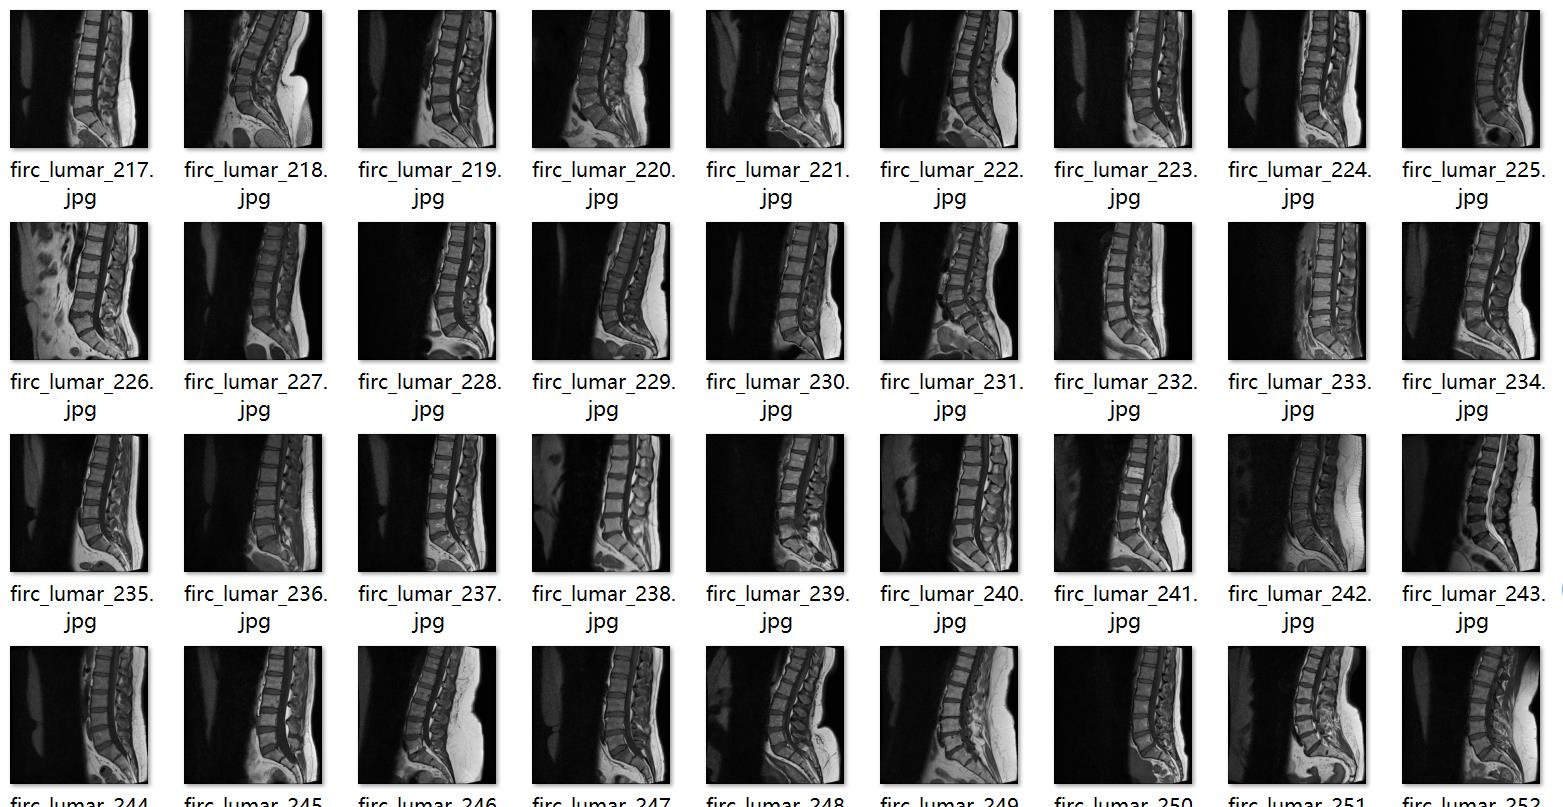

图片预览:

图片数量(jpg文件个数):514

图片分辨率:640x640